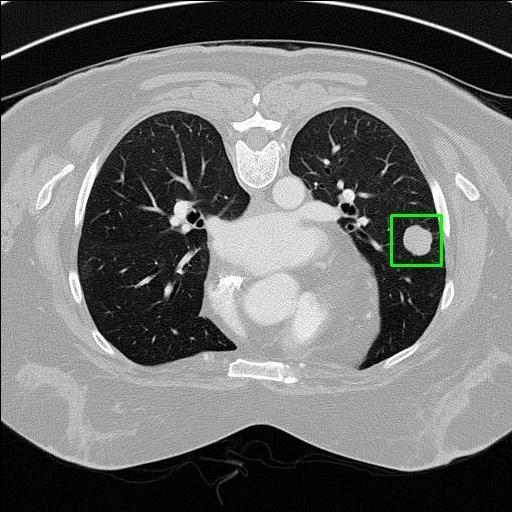

We developed an AI-based system using deep learning models for analyzing lung CT scans to detect and classify pulmonary nodules. We chose the YOLOv11 architecture for its enhanced object detection capability and adapted it specifically for medical imaging, incorporating pixel-level precision and severity classification.

Classification into three severity levels with colored bounding boxes.

Successfully built and deployed an AI model (YOLOv11) capable of detecting lung nodules in CT scans with high accuracy and real-time performance.

Designed a severity classification system that categorizes nodules into null, moderate, and severe using colored bounding boxes, assisting in rapid clinical decision-making.